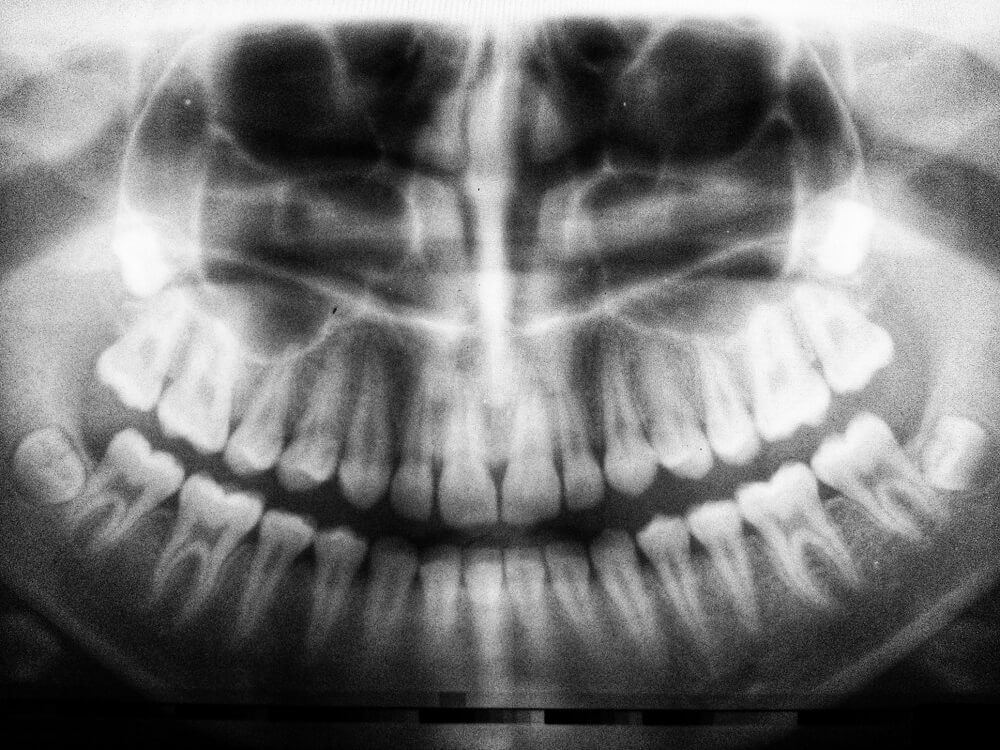

Wisdom teeth numbers in dental tooth system explained Artofit Is Laughing Gas Enough For Wisdom Teeth Is it right for your procedure? What's the difference between local and. Many oral surgery patients prefer laughing gas, or nitrous oxide. Wisdom teeth removal can be stressful, and laughing gas (nitrous oxide) is a safe, effective way to help you feel more. However, it is not always. Wisdom teeth removal with laughing gas (nitrous oxide) is designed to make. Is Laughing Gas Enough For Wisdom Teeth.